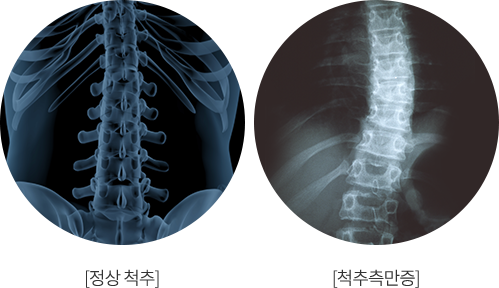

척추측만증

척앞이나 옆에서 전체 척추의 배열을 보았을 때 척추의 곡선이 과도하게 휘어진 질환

정상적인 척추는 전면 혹은 옆면에서 보았을 때 S형태를 이루고 있는데, 이러한 척추의 곡선이 변형되어

척추 특정 부위에 충격과 하중이 집중되고 통증이 발생하는 질환입니다.